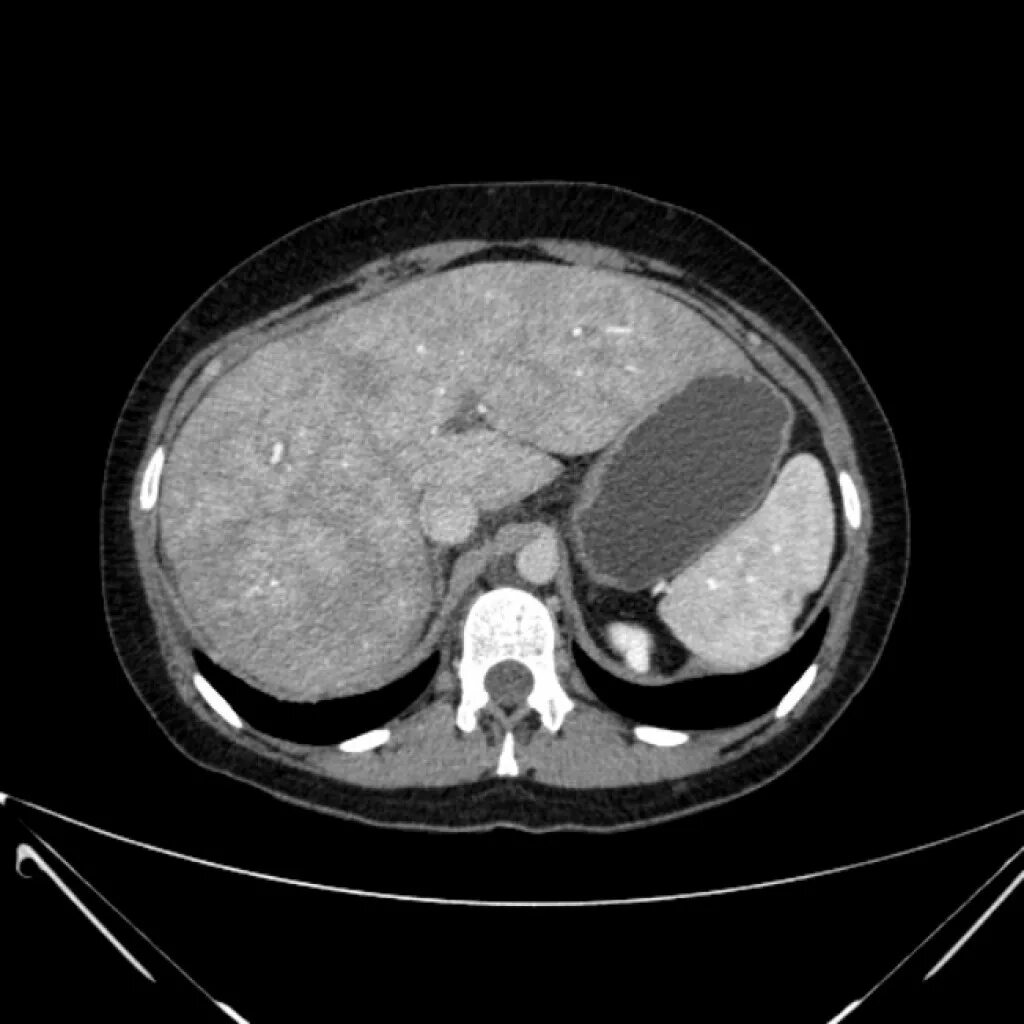

Диффузные изменения печени кт